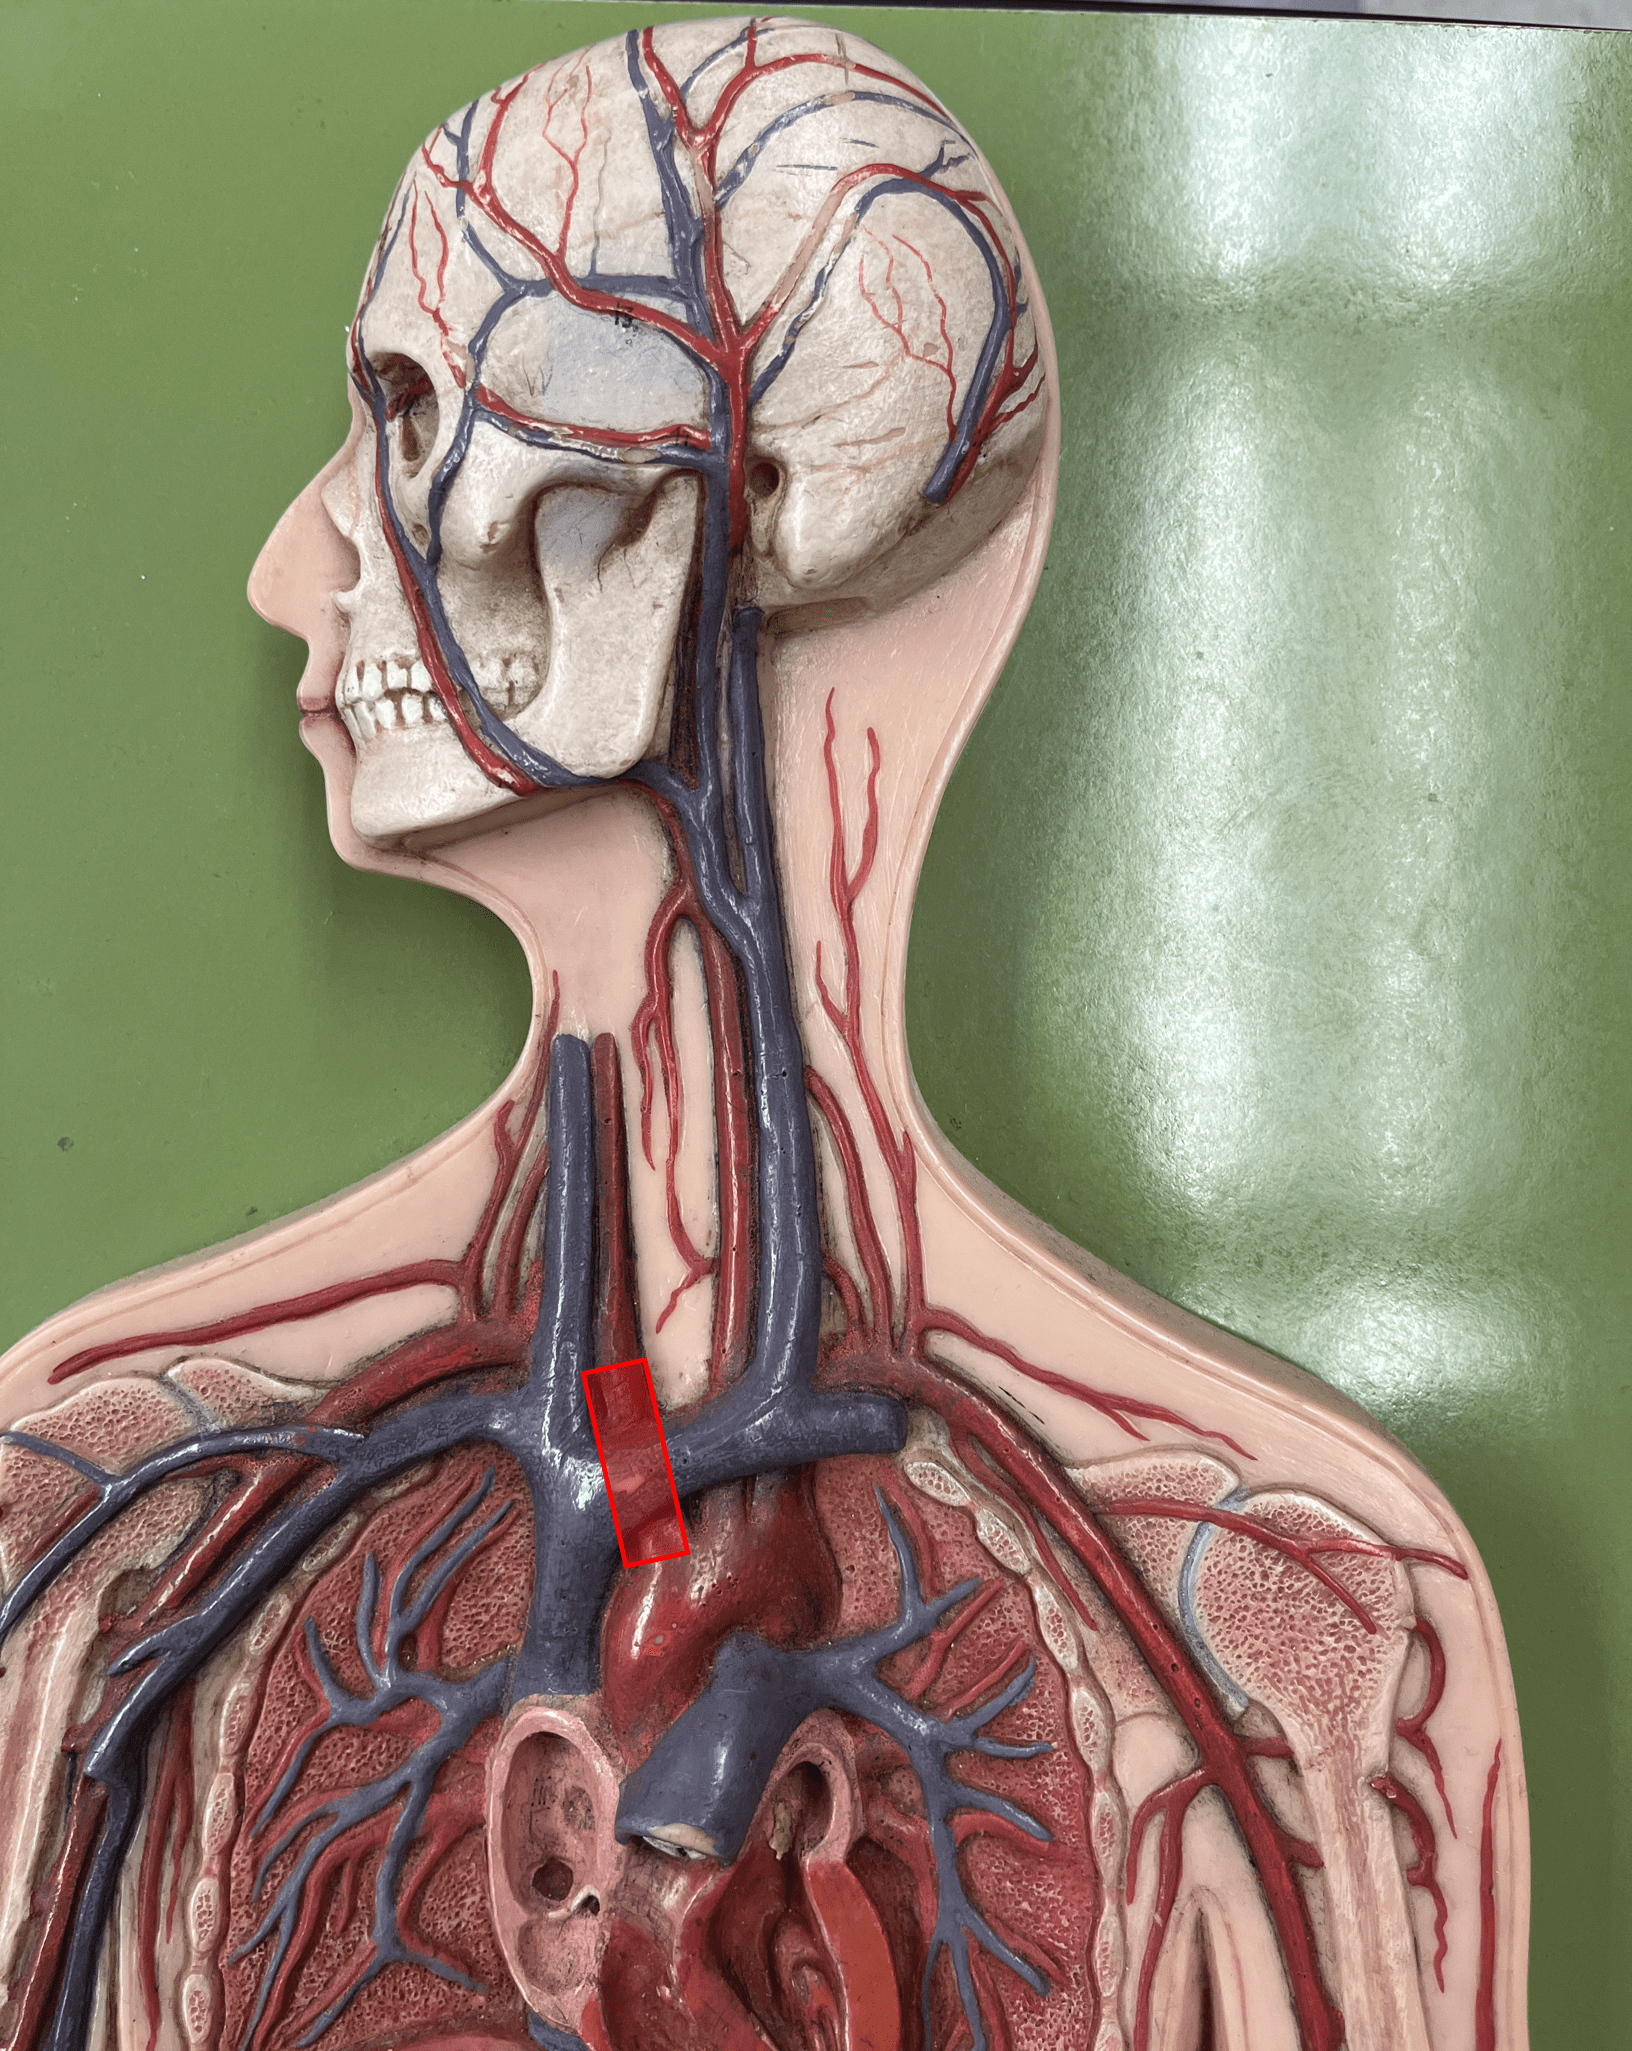

brachiocephalic vein

• A vein of the thorax.

• Drains the subclavian, external jugular, vertebral, internal jugular, and left intercostal (1-3) veins.

• Empties into the superior vena cava.

• Drains the subclavian, external jugular, vertebral, internal jugular, and left intercostal (1-3) veins.

• Empties into the superior vena cava.

superior vena cava

• A vein of the thorax.

• Drains the azygos and brachiocephalic veins.

• Empties into the right atrium.

• Drains the azygos and brachiocephalic veins.

• Empties into the right atrium.

subclavian vein

• A vein of the thorax.

• Drains the axillary vein.

• Empties into the brachiocephalic vein.

• Drains the axillary vein.

• Empties into the brachiocephalic vein.